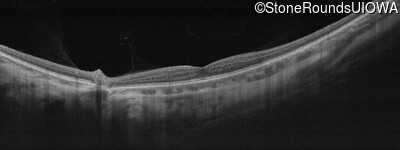

Age at visit: 26 years

This 26 year old man had significant myopia since childhood and uncorrectable reduction of acuity since his mid teens. Optic nerve abnormalities were noticed on a routine exam at age 5 and a diagnosis of Retinitis Pigmentosa was suggested. His medical history is also positive for profound hearing loss at birth and type 1 diabetes mellitus.

Age at visit: 29 years